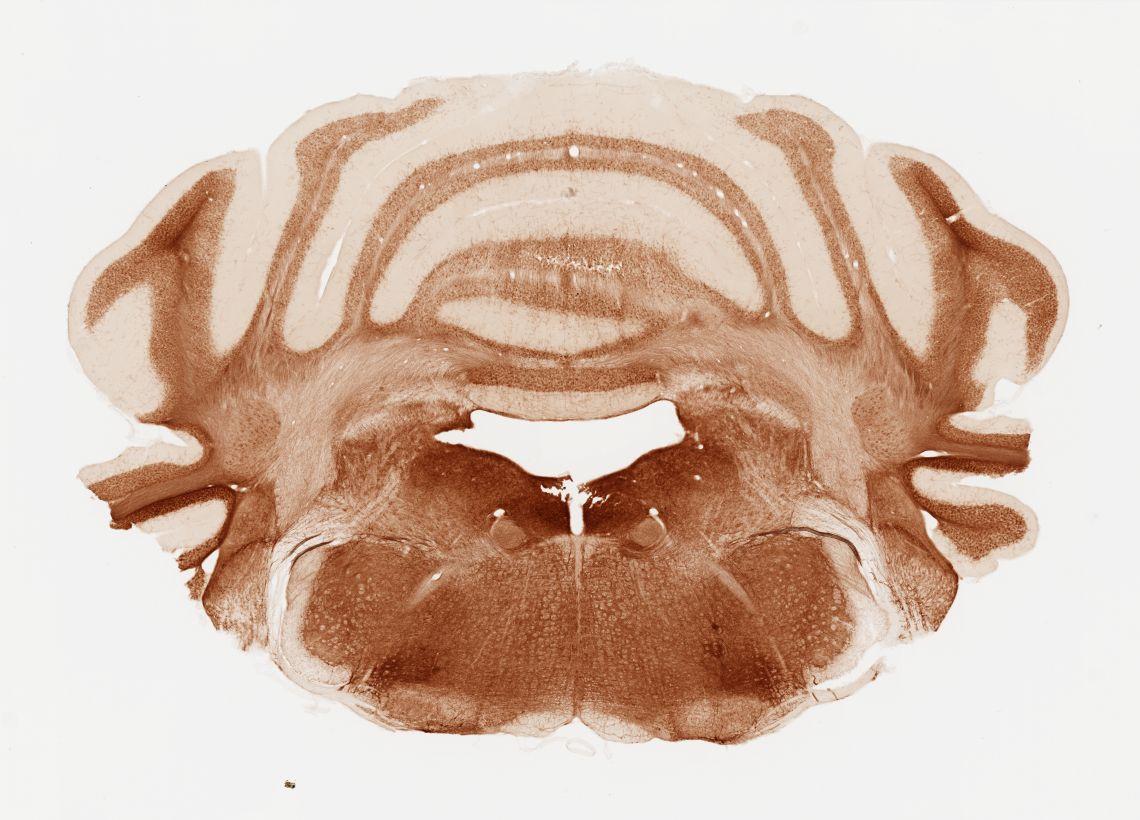

Datasets -> Mus Musculus -> AChE, (Acetyl Cholinesterase), coronal, histo, Whole-Brain, adult

[ Metadata ]   ·   Source: Shawn Mikula

Displaying Sections 41 thru 80 of 88 Sections for this Dataset